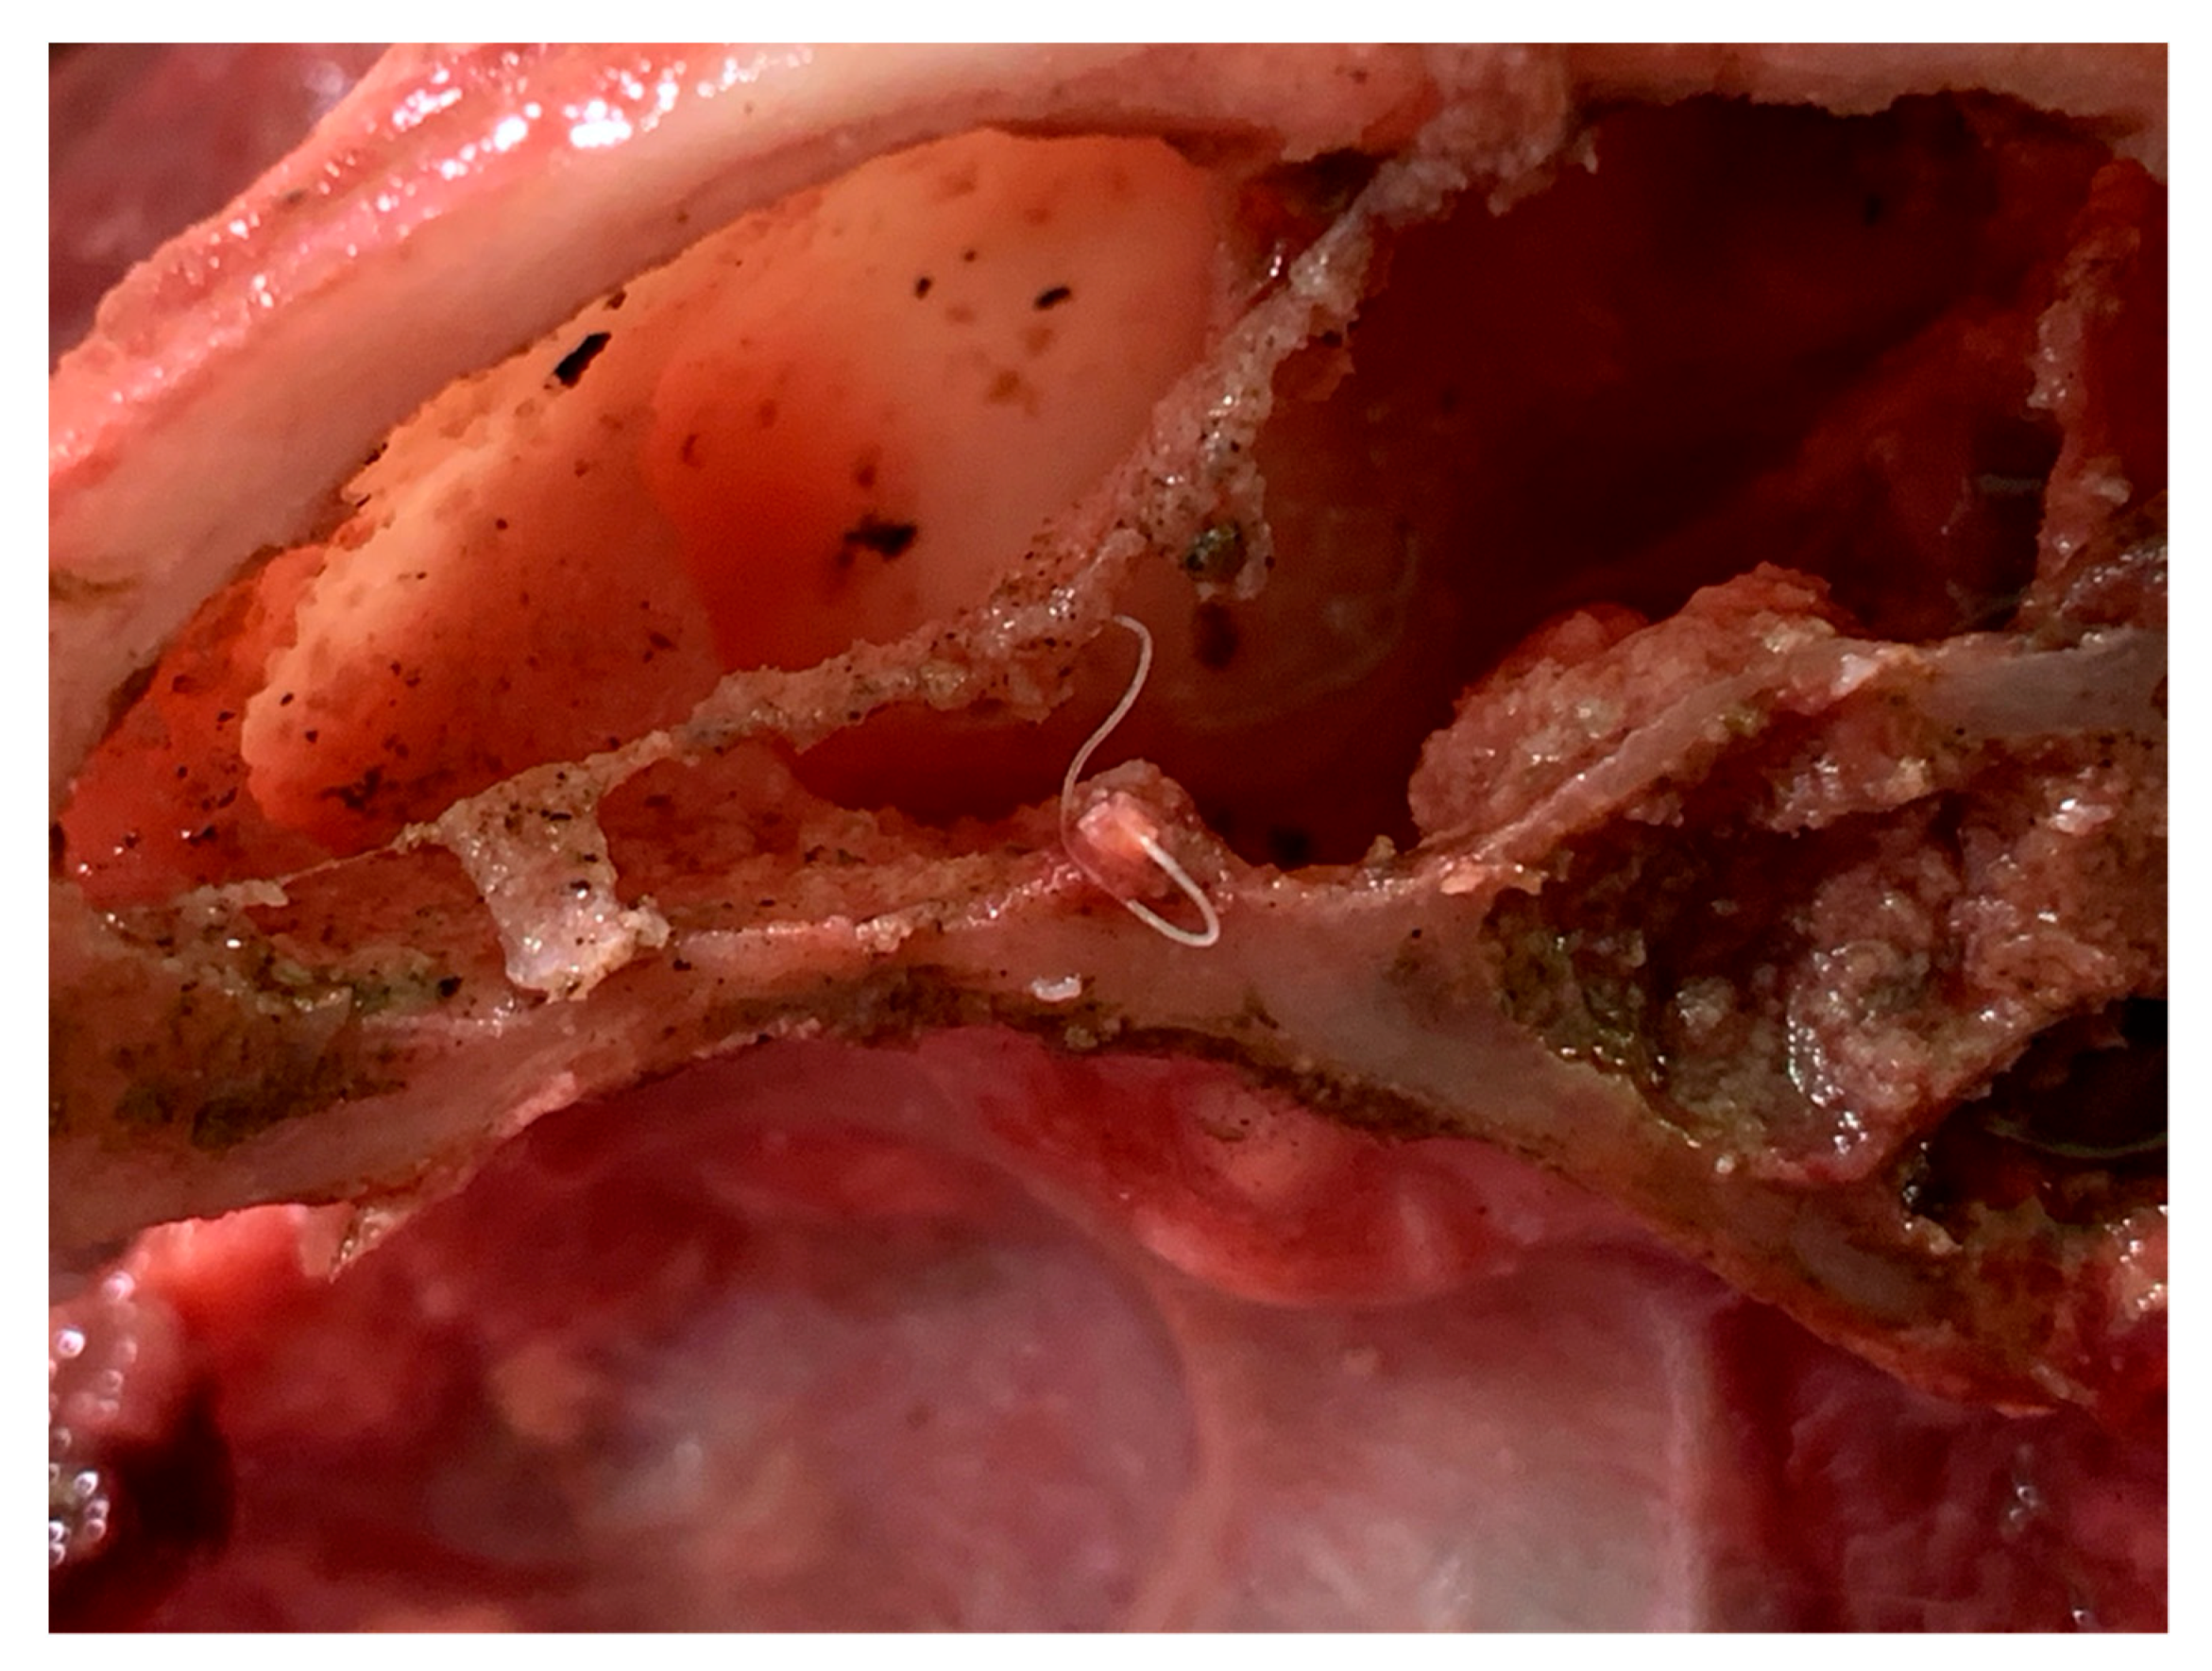

2.3. Parasitological Findings

2.4. Necroscopic Examination and Histopathology